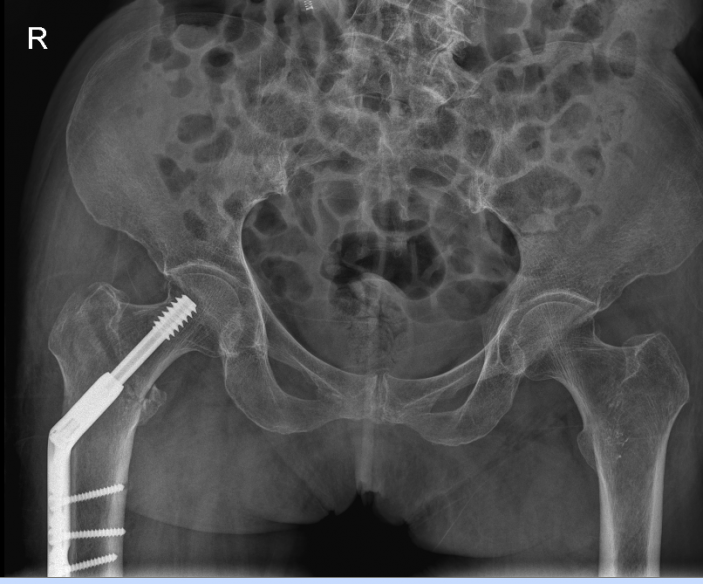

△右側(R)是賴婆婆3年前跌斷股骨術後,左側是本次手術術後。